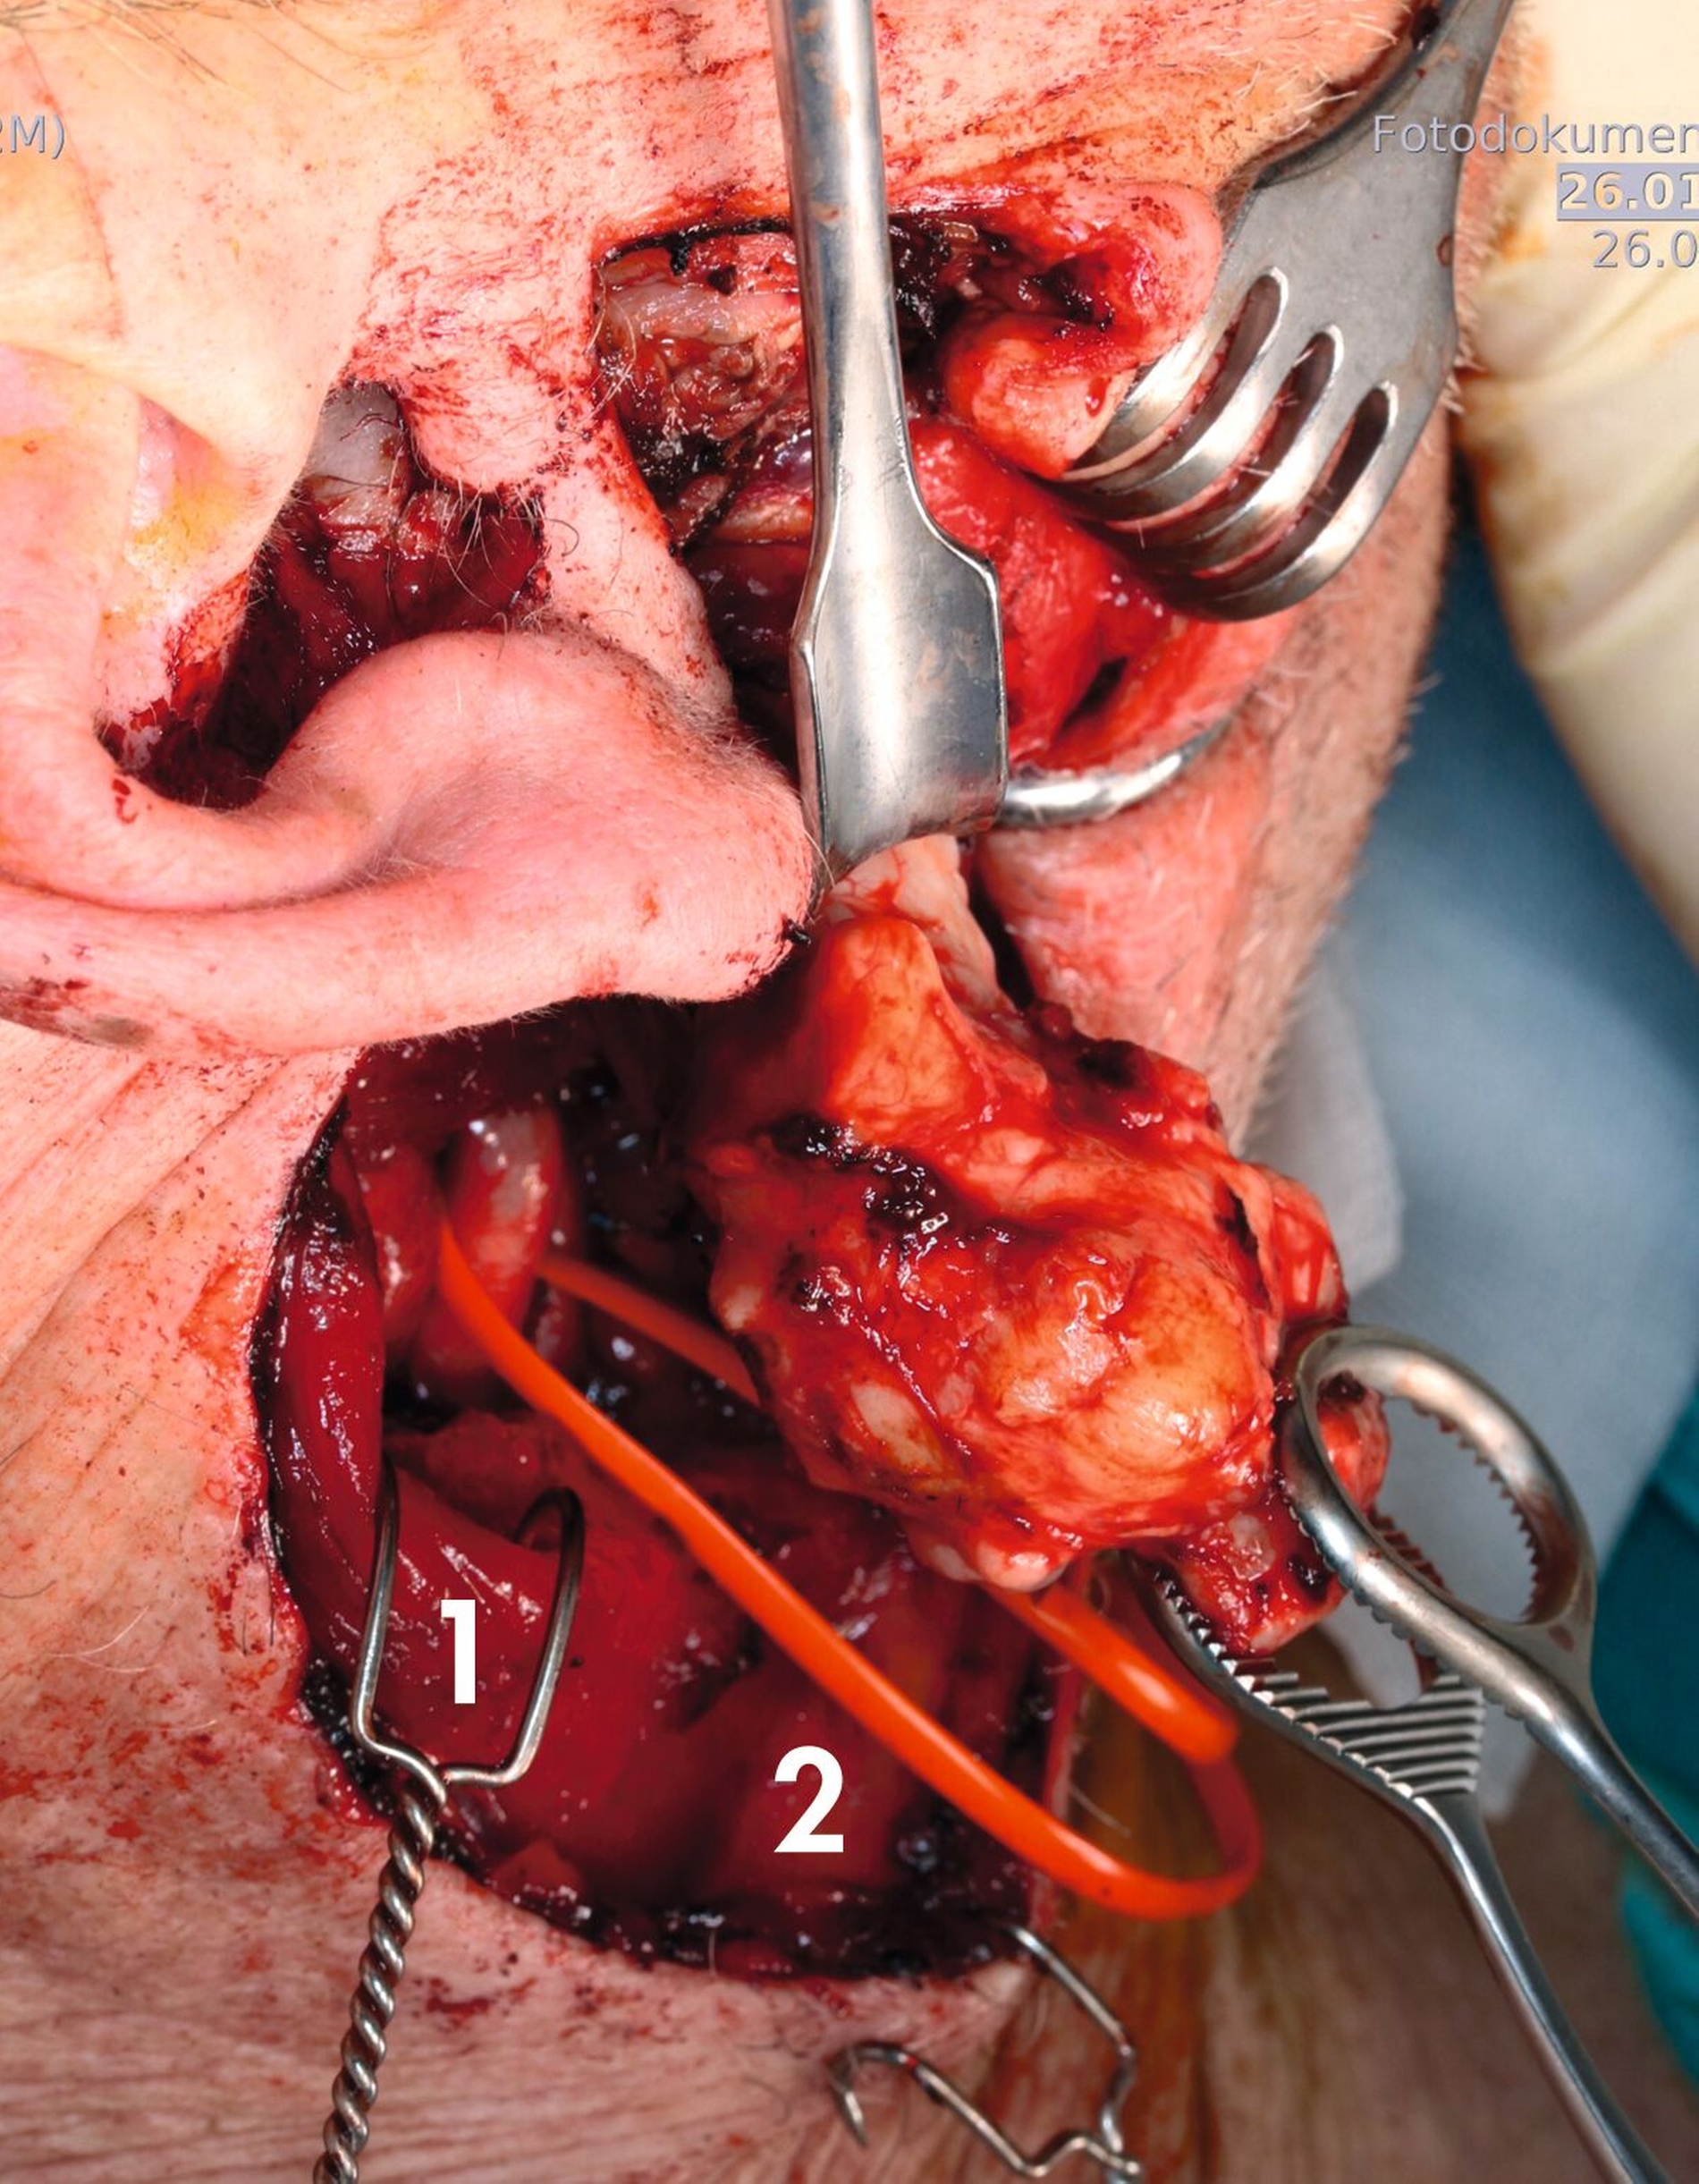

Präoperativ erfolgten die Anlage eines arteriellen Katheters, das Bereithalten von Erythrozytenkonzentraten sowie die Vorbereitung eines intraoperativen Nervenmonitorings. Nach präaurikulärem Hautschnitt mit kaudaler und anteriorer Erweiterung wurde das Platysma schichtweise präpariert. Der Hauptstamm des N. facialis wurde dargestellt und kontinuierlich überwacht.

Nach Darstellung der Gefäß‑Nerven‑Straße wurden die A. carotis communis sowie die A. carotis interna freipräpariert. Die A. carotis interna wurde vorsorglich mit einem Gefäßloop unterfahren und gesichert. Anschließend erfolgten die Mobilisation der Glandula parotis sowie die Darstellung des Kieferwinkels.

Nach subperiostaler Präparation wurde die geplante Osteotomie oberhalb des Foramen mandibulae angezeichnet. Zur späteren Reposition wurden vorab Osteosyntheseplatten angepasst, Schraubenlöcher vorgebohrt und das Material wieder entfernt. Die Osteotomie erfolgte mittels Säge unter Schutz der medialen Weichteile. Nach Distraktion des Osteotomiespalts mit einem Stromeyer-Haken bestand freie Sicht auf den Tumor.

Die Raumforderung präsentierte sich kapsuliert und verdrängend wachsend. Sie konnte unter Schonung der Nachbarstrukturen sorgfältig präpariert und vollständig in toto ohne Eröffnung der Kapsel entfernt werden. Dazu wurde zur Schonung der Gefäße mit dem Zeigefinger der Proc. Styloideus lokalisiert und mit der führenden Hand die stumpfe umrundende Präparation durchgeführt. Nach Einlage einer Drainage erfolgten die Reposition des Unterkiefers und die definitive Osteosynthese mit den zuvor adaptierten Osteosyntheseplatten. Der Wundverschluss erfolgte schichtweise.